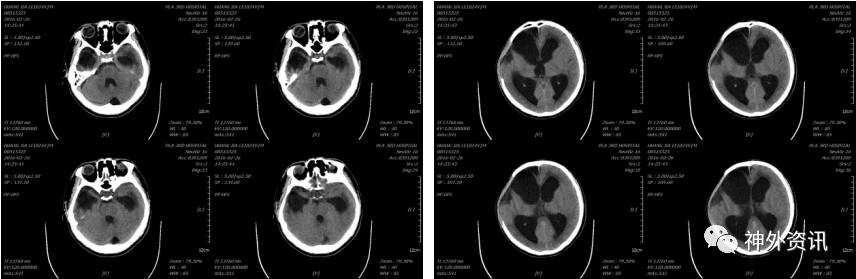

患者于2016-02-03能发简单“咿、啊”等音,但2016-02-26患者出现反应迟钝,大小便失禁等症状,复查头颅CT示(2016-02-26 14:25):

于2016-03-04在全麻下行颅骨钛网修补术,2016-03-05复查头颅CT示(2016-03-05 10:02):

术后患者反应迟钝、大小便失禁等症状缓解不明显,于2016-03-15在全麻下行脑室-腹腔分流术,术后复查头颅(2016-03-16 11:59)示: